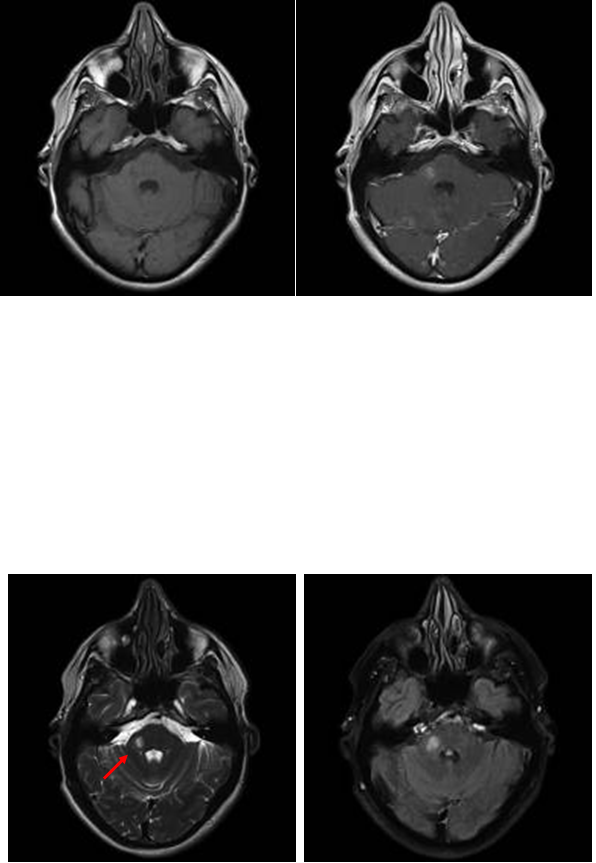

Tim 4G高密度一体化头颈线圈提供高分辨率头部成像,更多的线圈单元数支持更高的iPAT并行采集因子,有利于减少EPI序列的磁敏感伪影。

CASE 3:表皮样囊肿